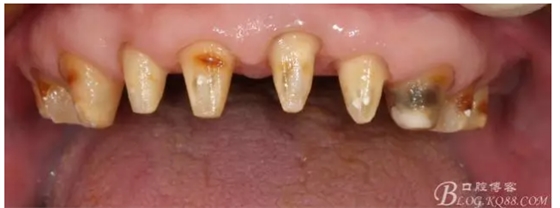

早期的病歷大約在2009年左右,那時只做了下頜的套筒冠

當(dāng)時勸病人上頜也做了修復(fù),但是病人感覺這樣還可以,把下面牙齒鑲好再說,雖然上面的牙齒不同程度的牙齦萎縮,都有些松動,但是患者年歲已高,只做下頜修復(fù)。囑咐病人半年復(fù)診一次,可是病人這一走就是2年,來要求制作上牙的修復(fù)

上牙出現(xiàn)了不同程度的牙齦萎縮